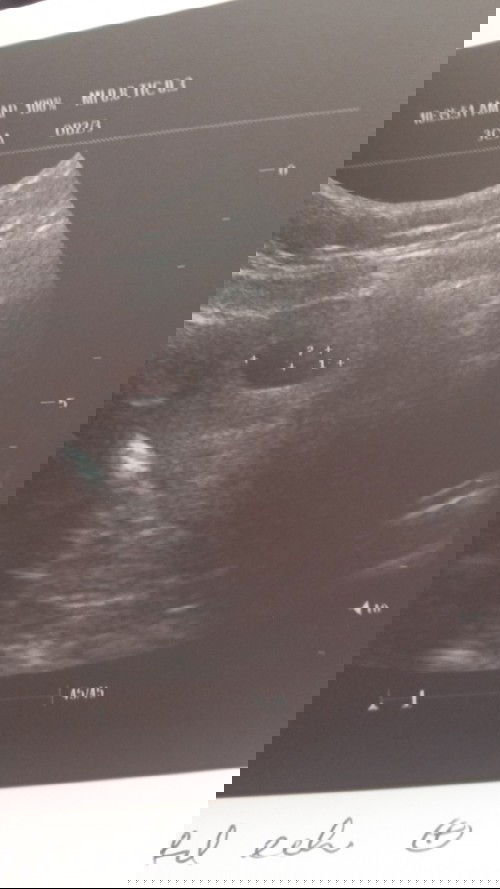

HAMIL 8W SCAN 6W

Hi mummy,,,scan doc tadi..ikut usia kandungan 8w4d .. bila scan jadi 6w4d.. ada ke mummy pernah berada dalam situasi saya.. #ingintahu #bantusharing #firstbaby #seriusnanya #1stimemom

sama macam saya sis haid tak regular ...scan 8 week jadi 6 week...dont worry banyakkan doa😊

dah sekarang dah 21 week alhamdulillah...